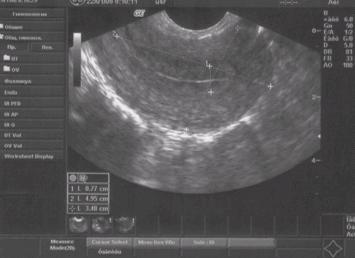

Ультразвуковое исследование покажет размеры матки, а опытный врач объяснит, каковы нормы ее размеров во время беременности, после родов и у девственниц. Фото УЗИ иллюстрирует размеры шейки матки, яичников и то, как выглядит матка, а врач даст полное описание изображению.

Осмотру подвергается тело матки, яичники, фаллопиевы трубы. Гинеколог при осмотре оценивает состояние матки, яичников и яйцеводов. Диагностике подлежит структура, форма, размер, толщина стенок, эхогенность, наличие визуально выраженных отклонений от нормы. Помимо этого, смотрят состояние шейки матки, ее длину и плотность.

Нормативные значения определены для всех органов брюшной полости: шейки матки, яичников, фаллопиевых труб и так далее.

При диагностике гинеколог сравнивает полученные данные с нормативными, оценивает текущее состояние и возраст женщины.